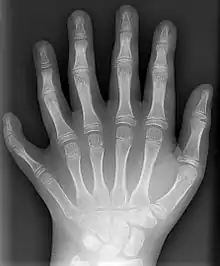

Полідактилія — Рентгенівський знімок 10-річного хлопчика